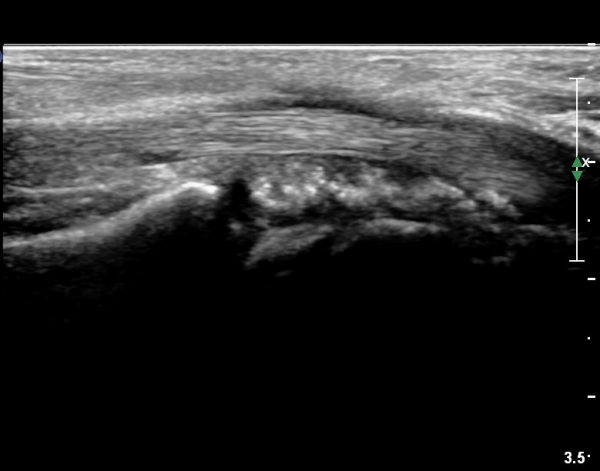

¼ö±Ù°ü ±ÙÀ§ºÎ Ⱦ´Ü¸é°Ë»ç¿¡¼ ±¼°î°Ç ½ÉºÎ¿¡ ¼®È¸È¼º À½¿µÀÌ Á¸ÀçÇϰí Àü¹ÝÀûÀÎ ¼öÁö ±¼°î°ÇÀÇ ºñÈÄ, Á¤Á߽ŰæÀÇ ºÎÁ¾°ú

ÈûÁÙ ¹× Á¤Á߽ŰæÀÇ Ç¥ÃþÀ¸·Î ÀüÀ§°¡ °üÂûµÈ´Ù, (»çÁø 3, 4,).